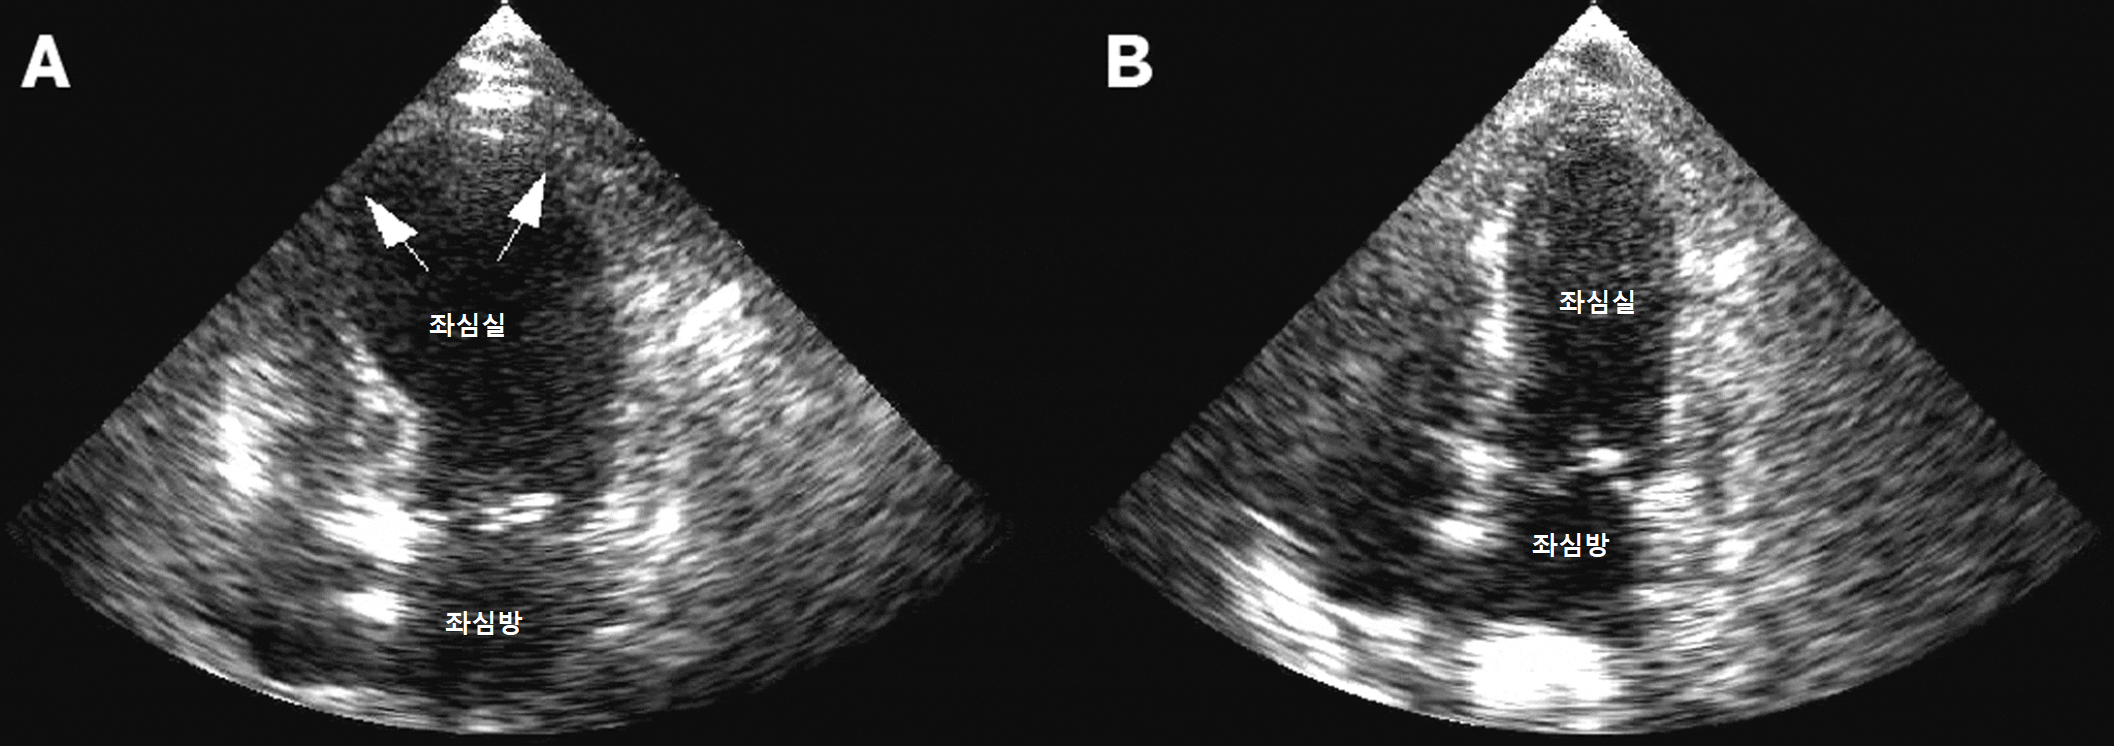

위 그림에서 보듯이 상심증후군의 심장의 좌심실은 일시적으로 늘어나게 되고, 수축력이 떨어지게 된다.

또한, 심장의 모양이나 기능을 평가하는 심장조영술/심초음파, 심장 MRI에서는 문어단지(takotsubo)처럼 생긴 확장된 좌심실의 모양과 함께 심근벽이 얇아진 소견이 관찰되며, 떨어진 좌심실 기능을 확인할 수 있다.